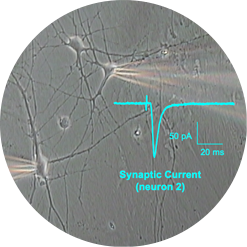

Patch Clamp recordings are performed with borosilicate electrodes of 1-2 μm tip diameter. A pipette containing an electrolyte solution is tightly sealed onto the neuronal membrane and isolates a part of the membrane (patch) electrically.

Currents fluxing through the channels in this patch flow into the pipette and can be recorded by an electrode that is connected to a highly sensitive differential amplifier. The pipette tip makes a giga-ohm seal contact with the neuronal membrane.

Patch Clamp recordings can be performed in different configurations:

• Single channel (as described above)

• Whole-cell (break of the cell membrane and access to the whole membrane conductancies)